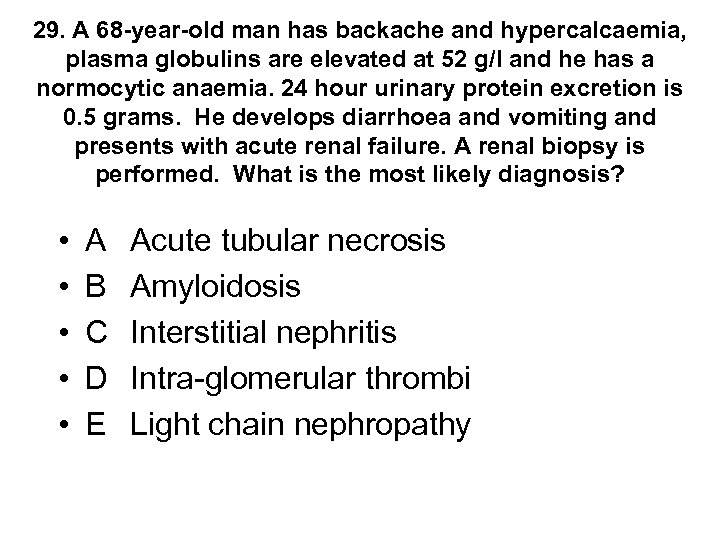

29. A 68 -year-old man has backache and hypercalcaemia, plasma globulins are elevated at 52 g/l and he has a normocytic anaemia. 24 hour urinary protein excretion is 0. 5 grams. He develops diarrhoea and vomiting and presents with acute renal failure. A renal biopsy is performed. What is the most likely diagnosis? • • • A B C D E Acute tubular necrosis Amyloidosis Interstitial nephritis Intra-glomerular thrombi Light chain nephropathy

29. A 68 -year-old man has backache and hypercalcaemia, plasma globulins are elevated at 52 g/l and he has a normocytic anaemia. 24 hour urinary protein excretion is 0. 5 grams. He develops diarrhoea and vomiting and presents with acute renal failure. A renal biopsy is performed. What is the most likely diagnosis? • • • A B C D E Acute tubular necrosis Amyloidosis Interstitial nephritis Intra-glomerular thrombi Light chain nephropathy

29. A 68 -year-old man has backache and hypercalcaemia, plasma globulins are elevated at 52 g/l and he has a normocytic anaemia. 24 hour urinary protein excretion is 0. 5 grams. He develops diarrhoea and vomiting and presents with acute renal failure. A renal biopsy is performed. What is the most likely diagnosis? • • • A B C D E Acute tubular necrosis Amyloidosis Interstitial nephritis Intra-glomerular thrombi Light chain nephropathy

29. A 68 -year-old man has backache and hypercalcaemia, plasma globulins are elevated at 52 g/l and he has a normocytic anaemia. 24 hour urinary protein excretion is 0. 5 grams. He develops diarrhoea and vomiting and presents with acute renal failure. A renal biopsy is performed. What is the most likely diagnosis? • • • A B C D E Acute tubular necrosis Amyloidosis Interstitial nephritis Intra-glomerular thrombi Light chain nephropathy

Myeloma • Aetiology of renal failure • - nephrotoxicity due to free light chains • - also dehydration, hypercalcaemia, infection, amyloid, hyperuricaemia • Presentation • - AKI or CRF • - Hypercalcaemia and low platelets are important clues to diagnosis in renal failure • Diagnosis • - 10% clonal bone marrow plasma cells plus • - Monoclonal protein in serum or urine plus/minus • - Myeloma related organ dysfunction: hypercalcaemia, renal insufficiency, anaemia, bone disease (lytic lesions) • - renal biopsy not mandatory, usually shows light chain nephropathy

Myeloma • Aetiology of renal failure • - nephrotoxicity due to free light chains • - also dehydration, hypercalcaemia, infection, amyloid, hyperuricaemia • Presentation • - AKI or CRF • - Hypercalcaemia and low platelets are important clues to diagnosis in renal failure • Diagnosis • - 10% clonal bone marrow plasma cells plus • - Monoclonal protein in serum or urine plus/minus • - Myeloma related organ dysfunction: hypercalcaemia, renal insufficiency, anaemia, bone disease (lytic lesions) • - renal biopsy not mandatory, usually shows light chain nephropathy